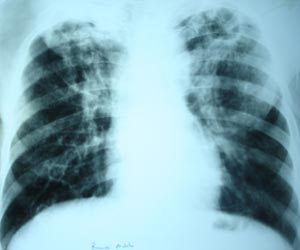

Pulmonary Koch’s with cavitation

A thin walled cavity is visible in left upper zone with bilateral fibronodular Infiltration. Cavity always suggest of serious parenchymal disease.